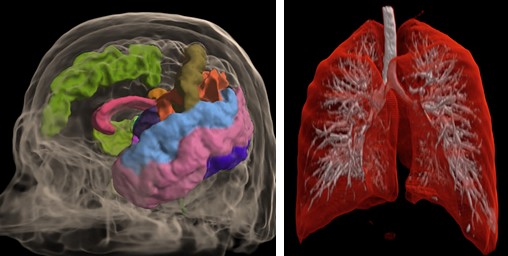

Volume Visualization¶

This method suits for studying the initial data volume and the soft tissues visualization. It allows to choose an area of the interest by specifying the transfer function, which assigns the amount of the initial data to the amount of the transparency and color. To simplify the transfer function, the user uses a function in the application. The user can define this function by adjusting three parameters (a, b, and c) with sliders. The function is nonzero only if the intensity i satisfies the conditions a < i < b or i > c. When the function satisfies the first condition, the user can determine the transparency value by the value of the additional slider, and when it satisfies the second one, the transparency value is considered equal to 1. Such a subset of transfer functions is sufficient to visualize the overwhelming array of medical data. The base of this method is the calculation of the volume integral along the rays passing through the pixels.

Segmented Data Visualization¶

User can select ROI (Region of Interest) during segmented data visualization.

Automatic Segmentation¶

Special automatic segmentation methods are implemented for the lungs data and skull tissues separation from brain.